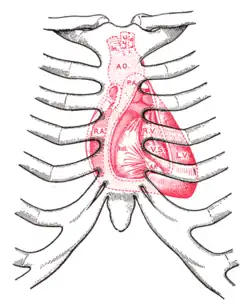

Ictus cordis (termo latino, não confundir com a palavra inglesa ictus que significa deficiência neurológica localizada de aparecimento agudo), choque da ponta ou impulso apical é o local da parede torácica onde se pode palpar o pulsar do coração. A localização usual depende do tipo morfológico da pessoa. Num indivíduo normolíneo situa-se a nível da interseção do 4º ou 5º espaço intercostal esquerdo com a linha médio-clavicular esquerda. Este ponto corresponde à zona onde o coração está mais próximo da grelha costal permitindo assim a sua palpação num espaço intercostal.[1]

- No tipo normolíneo o impulso apical é sentido na sua localização habitual, interseção da linha médio-clavicular esquerda com o 4º ou 5º espaço intercostal.

- No tipo longilíneo, indivíduos altos, magros, com uma distância púbis-pé superior à distância púbis-vértice da cabeça, tórax estreito, ombros estreitos, o coração adopta uma posição mais vertical tendo na radiografia torácica o aspeto chamado de "coração em gota". A ponta cardíaca desce abaixo do 5º espaço intercostal, mais central que a linha médio-clavicular e o impulso apical é por vezes sentido próximo do apêndice xifoide esternal.

- No morfotipo brevilíneo, indivíduos com o tórax largo, uma distância púbis-pé menor que a distância púbis-vértice, muitas vezes com excesso de peso e um diafragma elevado, o coração está numa posição mais horizontal. O impulso apical é desviado para acima do 4º espaço intercostal e para fora da linha médio-clavicular, na linha axilar anterior e mesmo por vezes na linha axilar média. Numa radiografia do tórax o coração aparece "deitado" sobre o diafragma dando um falso aspecto de dilatação cardíaca porque o índice cardiotorácico (sinal radiológico: razão entre o diâmetro do coração e o diâmetro torácico) está aumentado.[2]